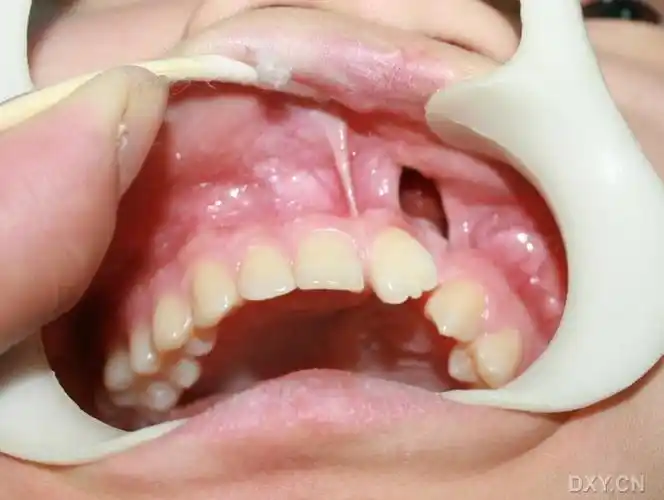

牙齿有裂缝,一咬硬物就痛

【求助】牙槽嵴裂术中的照片